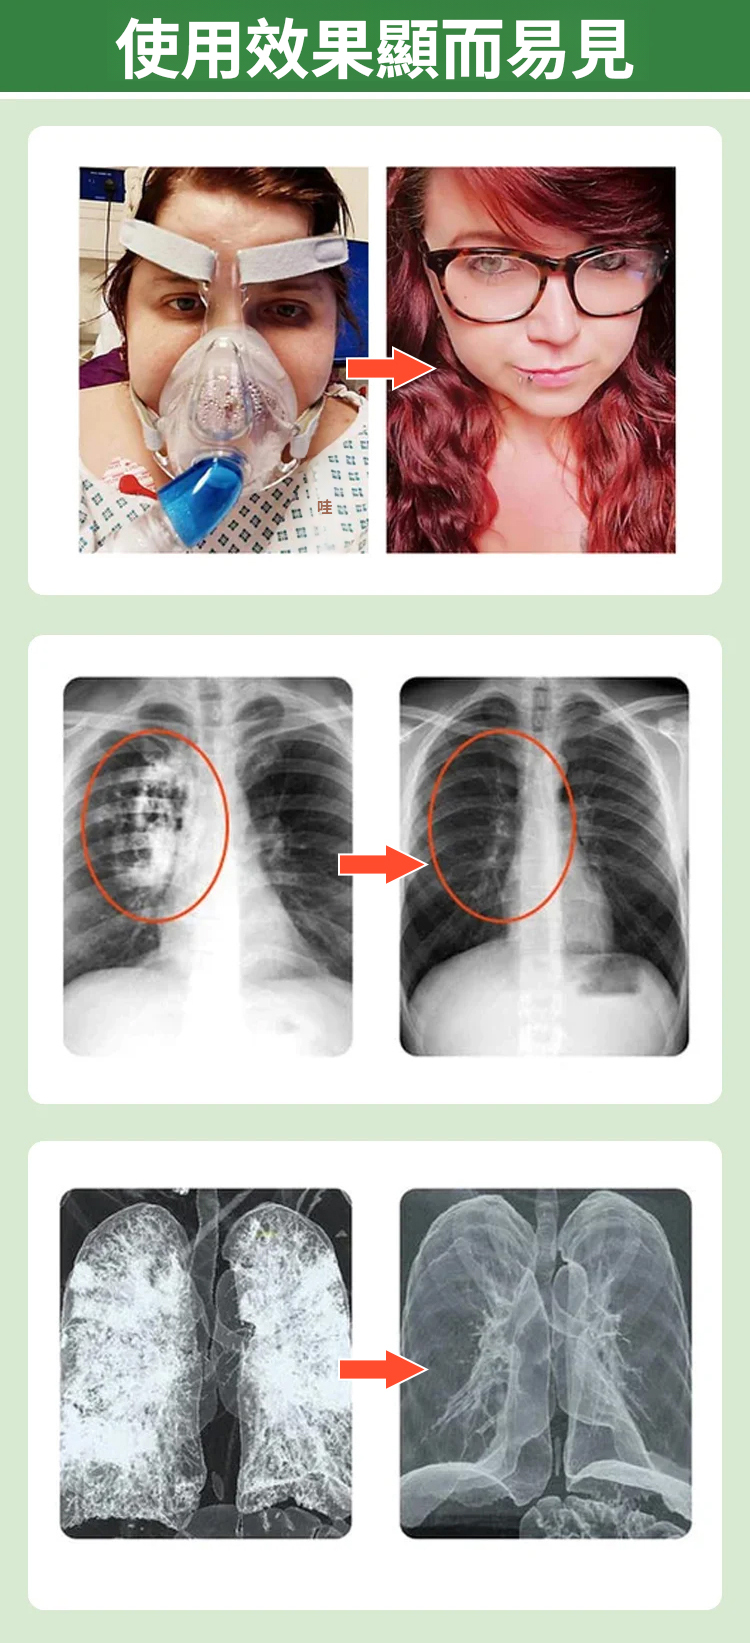

【止咳潤肺】麥冬枇杷葉雪梨片

245bd3dd413f7f4eb6aa7950bdaf832b.gif